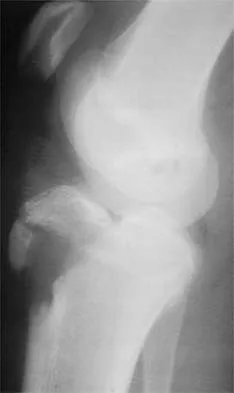

Question 24

The essential lesion responsible for posterolateral rotatory instability of the elbow is disruption of the